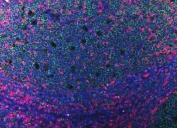

CD3 epsilon is a polypeptide which in humans is encoded by the CD3E gene which resides on chromosome 11. It is mapped to 11q23.3. Together with CD3gamma, -delta and -zeta, and the T-cell receptor alpha/beta and gamma/delta heterodimers, CD3e forms the T cell receptor-CD3 complex. This complex plays an important role in coupling antigen recognition to several intracellular signal-transduction pathways. The genes encoding the e, g and d polypeptides are located in the same cluster on chromosome 11. The e-polypeptide plays an essential role in T-cell development.